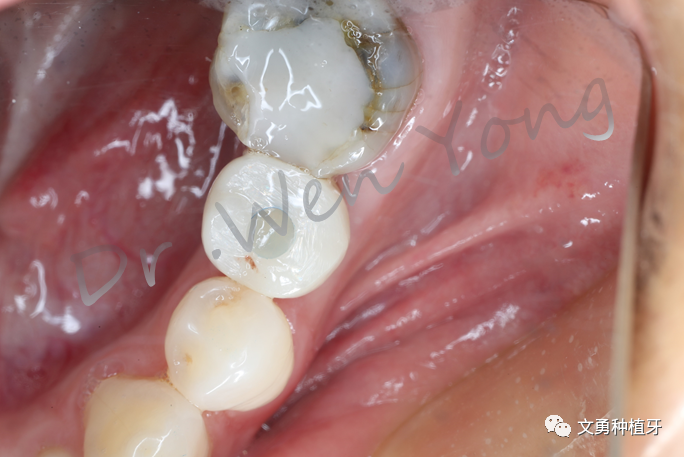

①取出个性化愈合基台后,植体袖口健康

②修复体就位

③附着龈充足